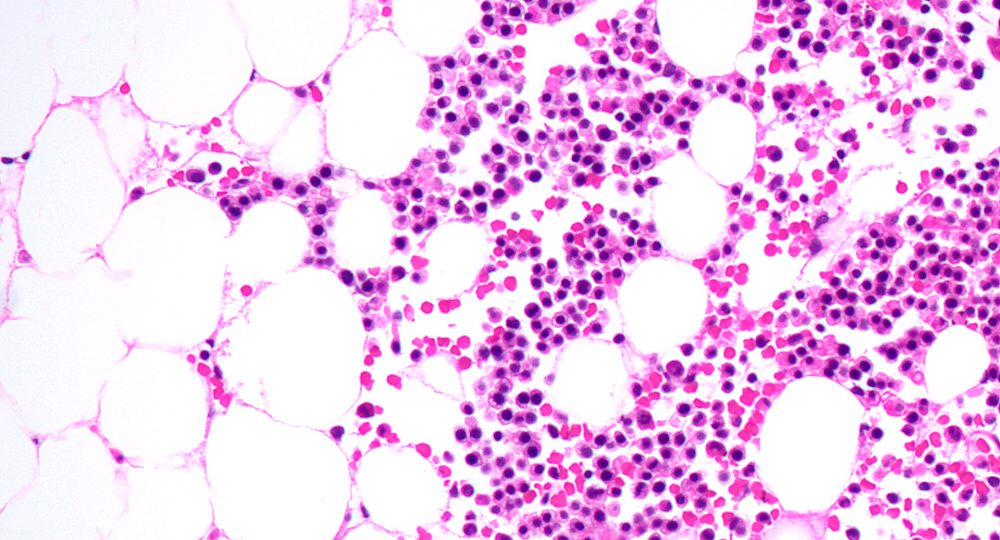

Combination therapy well-tolerated and highly effective for patients with IDH1-mutated acute myeloid leukemia (AML)

ABSTRACT: #7500

A combination therapy of ivosenidib (IVO) plus venetoclax (VEN) with or without azacitidine (AZA) was found to be effective...